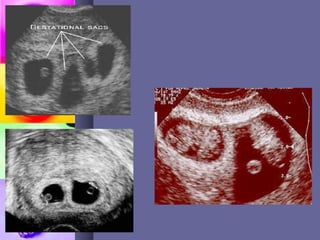

Beta HCG – much higher forBeta HCG – much higher for

gestation. Ultrasoundgestation. Ultrasound

DIAGNOSISDIAGNOSIS ♣♣ Symptoms &SignsSymptoms & Signs  hyperemesis gravidarumhyperemesis gravidarum  excessive weight gainexcessive weight gain  fetal movts felt infetal movts felt in differentdifferent parts of theparts of the abdomenabdomen  uterus larger than datesuterus larger than dates Beta HCG – much higher forBeta HCG – much higher for gestation. Ultrasoundgestation. Ultrasound